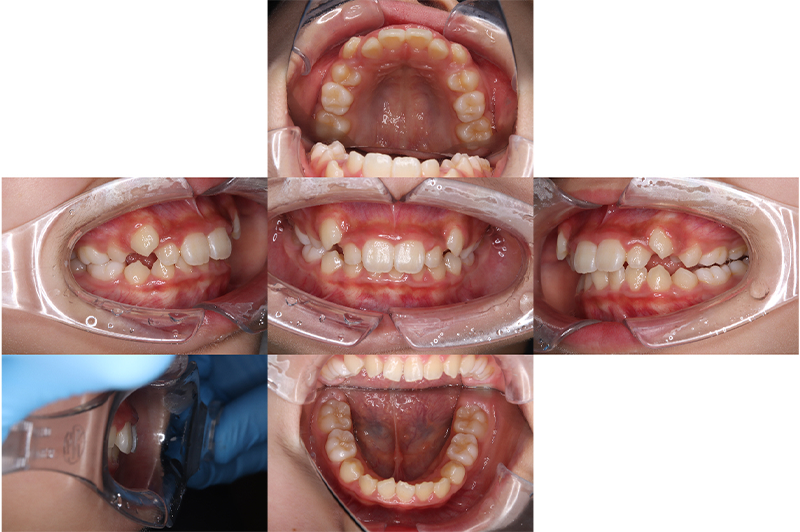

症例叢生

性別

期間7年7ヶ月

治療内容N-Bimler装置、Neo-Capを使用して治療

治療における

副作用・リスク

装着しないと効果は出ません

金額ビムラー装置:550,000円

ネオキャップ:4本

合計:572,000円